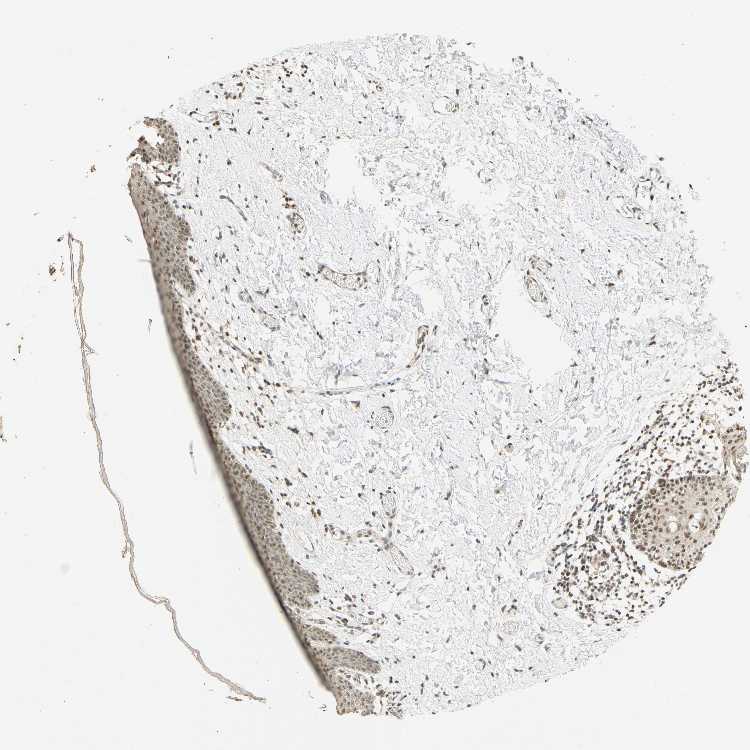

SKIN 2 - Antibody stainingi

Antibody staining in the annotated cell types in the current human tissue is reported as not detected, low, medium, or high, based on conventional immunohistochemistry profiling in selected tissues. This score is based on the combination of the staining intensity and fraction of stained cells.

Each image is clickable and will lead to virtual microscopy that enables deeper exploration of all samples and also displays staining intensity scores, fraction scores and subcellular localization as well as patient and tissue information for each sample.

Antibody HPA018248Antibody HPA019127Antibody CAB009196

Cells in basal layer Medium--

Cells in corneal layer Not detected--

Cells in granular layer Medium--

Cells in spinous layer Medium--

Endothelial cells Medium--

Epidermal cells -HighMedium

Extracellular matrix Not detected--

Fibrohistiocytic cells Medium--

Langerhans cells Medium--

Lymphocytes High--

Melanocytes High--

Vascular mural cells Not detected--